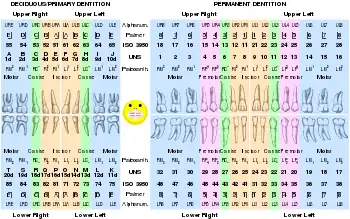

Table of codes

| Permanent teeth | |||||||||||||||

|---|---|---|---|---|---|---|---|---|---|---|---|---|---|---|---|

| patient's upper right | patient's upper left | ||||||||||||||

| 18 | 17 | 16 | 15 | 14 | 13 | 12 | 11 | 21 | 22 | 23 | 24 | 25 | 26 | 27 | 28 |

| 48 | 47 | 46 | 45 | 44 | 43 | 42 | 41 | 31 | 32 | 33 | 34 | 35 | 36 | 37 | 38 |

| patient's lower right | patient's lower left | ||||||||||||||

| Deciduous teeth (baby teeth) | |||||||||||||||

| upper right | upper left | ||||||||||||||

| 55 | 54 | 53 | 52 | 51 | 61 | 62 | 63 | 64 | 65 | ||||||

| 85 | 84 | 83 | 82 | 81 | 71 | 72 | 73 | 74 | 75 | ||||||

| lower right | lower left | ||||||||||||||

Codes, names, and usual number of roots: (see chart of teeth at Universal Numbering System)

- 11 21 51 61 maxillary central incisor 1

- 41 31 81 71 mandibular central incisor 1

- 12 22 52 62 maxillary lateral incisor 1

- 42 32 82 72 mandibular lateral incisor 1

- 13 23 53 63 maxillary canine 1

- 43 33 83 73 mandibular canine 1

- 14 24 maxillary first premolar 2

- 44 34 mandibular first premolar 1

- 15 25 maxillary second premolar 1

- 45 35 mandibular second premolar 1

- 16 26 54 64 maxillary first molar 3

- 46 36 84 74 mandibular first molar 2

- 17 27 55 65 maxillary second molar 3

- 47 37 85 75 mandibular second molar 2

- 18 28 maxillary third molar 3

- 48 38 mandibular third molar 2